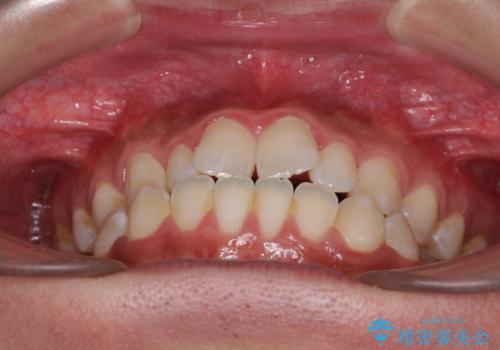

- 受け口傾向の咬み合わせと口元の突出感を気にして来院された患者様です。

受け口傾向特有の狭い上顎歯列であったため、歯列の拡大を補助装置で行い、下顎歯列全体を後方に移動させることとしました。

下顎の残存乳歯は小臼歯よりも大きいため、スペースを閉じるために長い期間を必要としますが、予想通りに長期間を要することとなりました。

受け口傾向の方の抜歯矯正は、下顎前歯が舌側に倒れることで歯肉退縮を起こしやすいことが知られていますが、ワイヤーに工夫をすることでリスクを軽減させています。